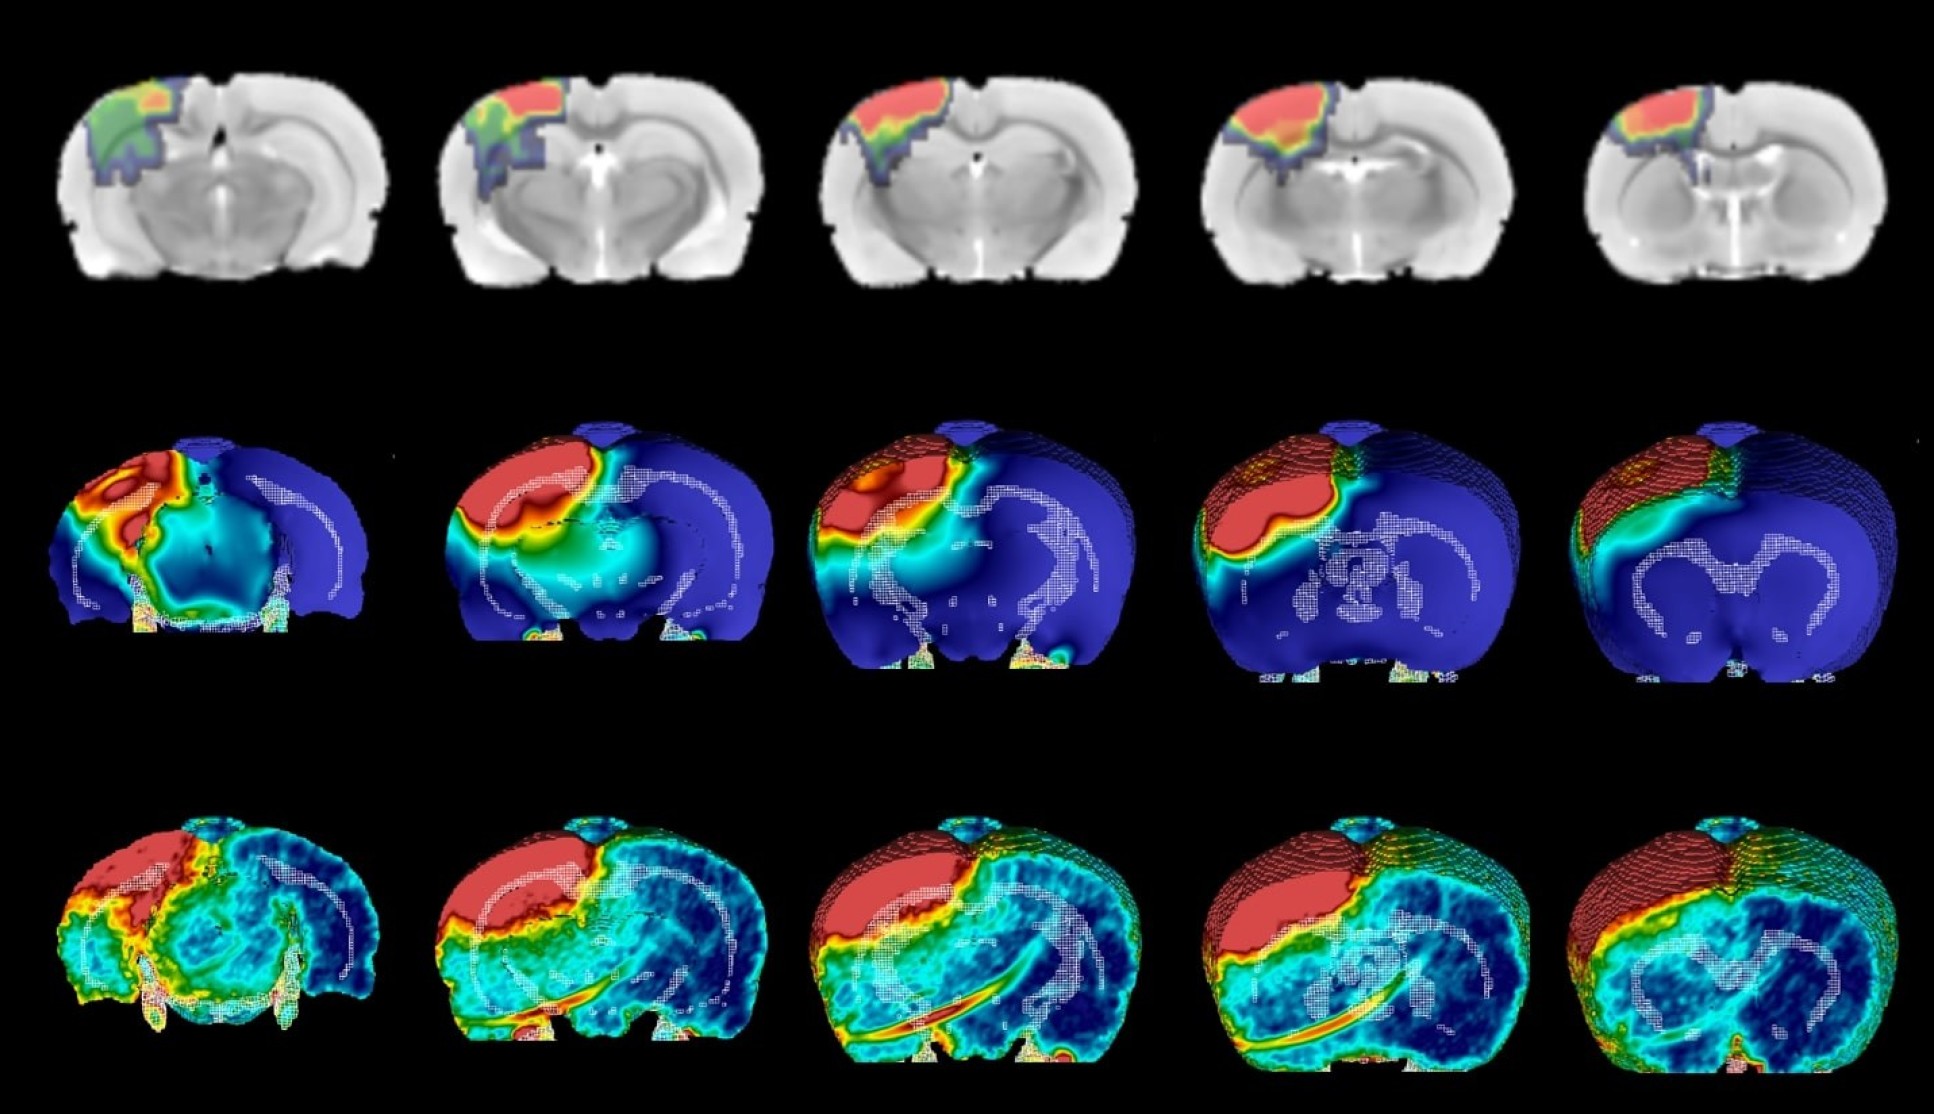

10 brainy and mental health stories from 2021